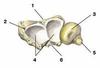

Upper Limb Flashcards

(26 cards)

1

2

3

4

4

5

6

7

8

9

10

11

12

13

14

15

16

17

18

19

20

21

22

23

24

25

Trochlea

26

Trochlear Notch